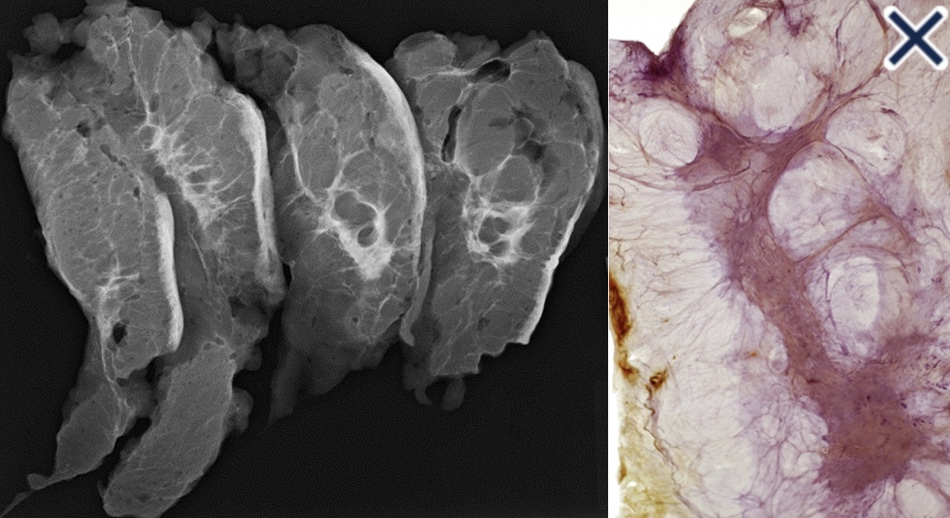

- The subgross (3D) histopathology images:

- Show how growth of the mesenchymal tissue distorts the normal, harmonious connective tissue framework:

- By causing nonuniform thickening of the fine sheets of connective tissue